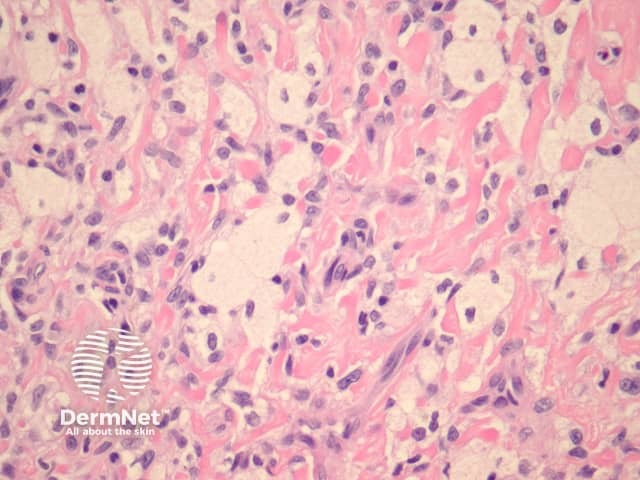

Histologically, there are cleft-like haemorrhagic spaces within the centre of the aneurysmal dermatofibroma that mimic vessels but lack an endothelial lining. The tumour itself tends to be fairly cellular (figure 7, 8). Haemosiderin deposition may be an additional feature. Aneurysmal dermatofibroma may be mistaken for a vascular tumour, however, clues to the diagnosis include surrounding features of dermatofibroma, and endothelial cell markers are positive in normal vessels only and not the aneurysmal spaces.

Figure 7

Figure 8